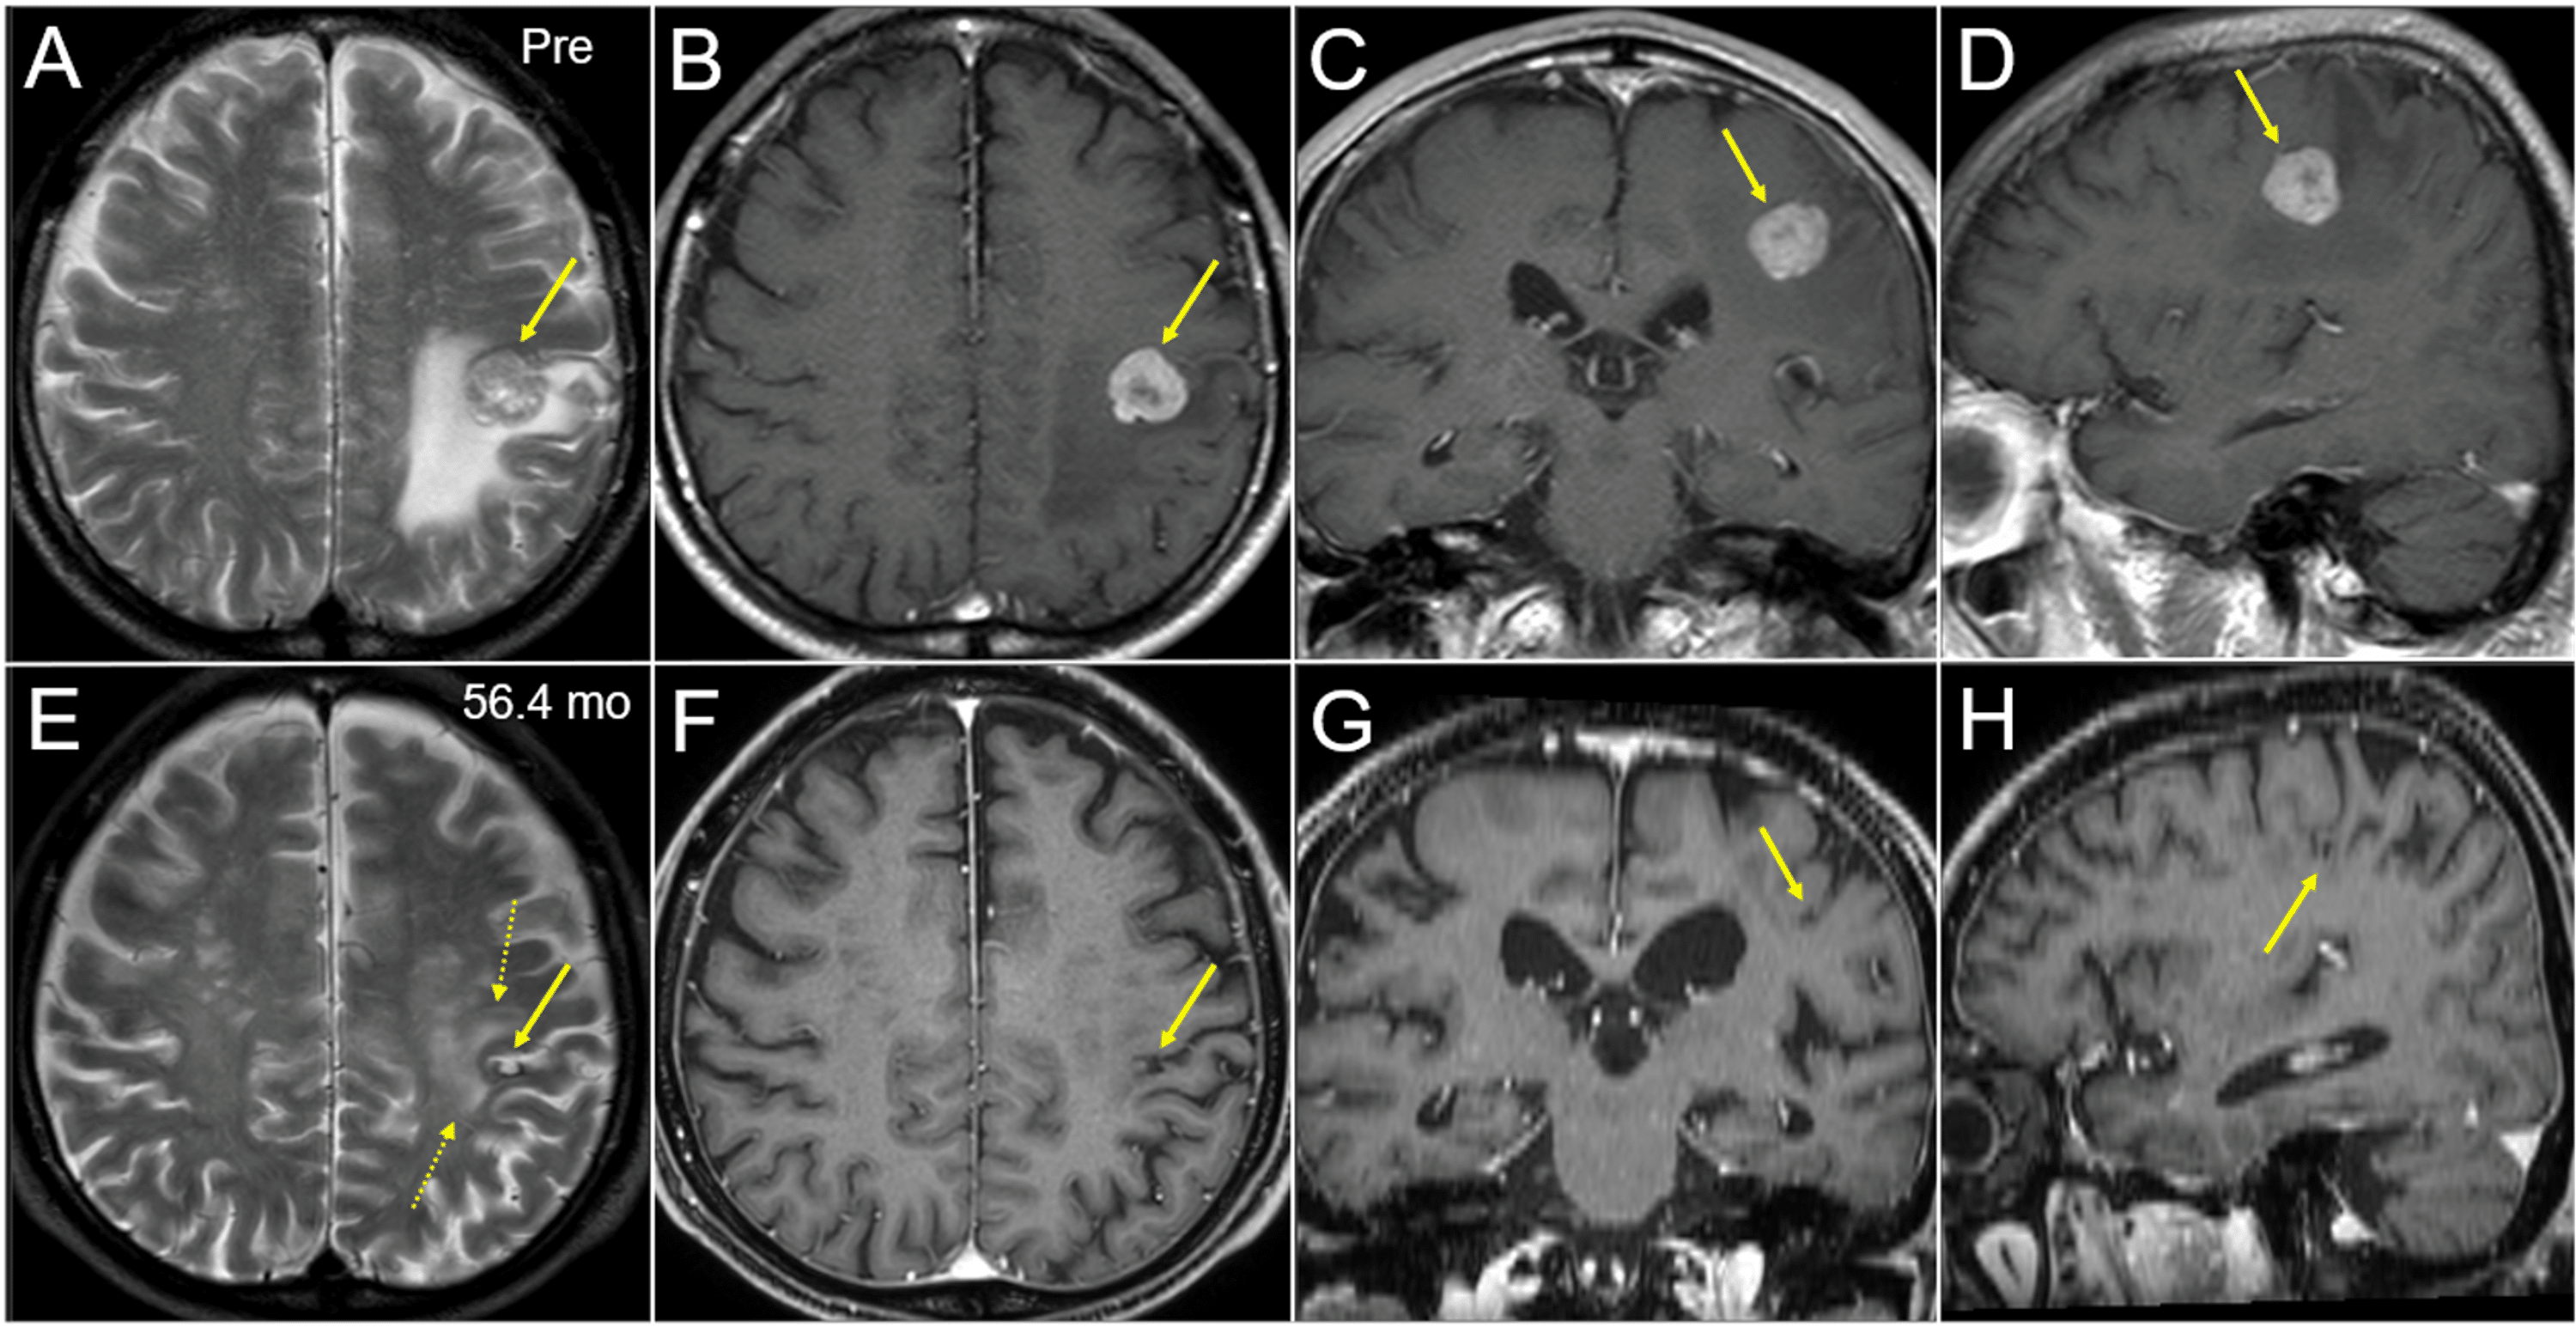

Cureus FiveYear Sustained Complete Remission With Minimal Adverse Radiosurgery Protons For many patients, stereotactic radiosurgery (srs) offers a minimally invasive, curative option when surgical techniques are not. Web in preparing to use protons in radiosurgery and radiotherapy, radiobiological effects of protons were studied extensively by. Web despite requiring specialized facilities for its generation and manipulation, proton radiation offers superior dose conformality relative. Part i deals with the relevant physics and. Radiosurgery Protons.